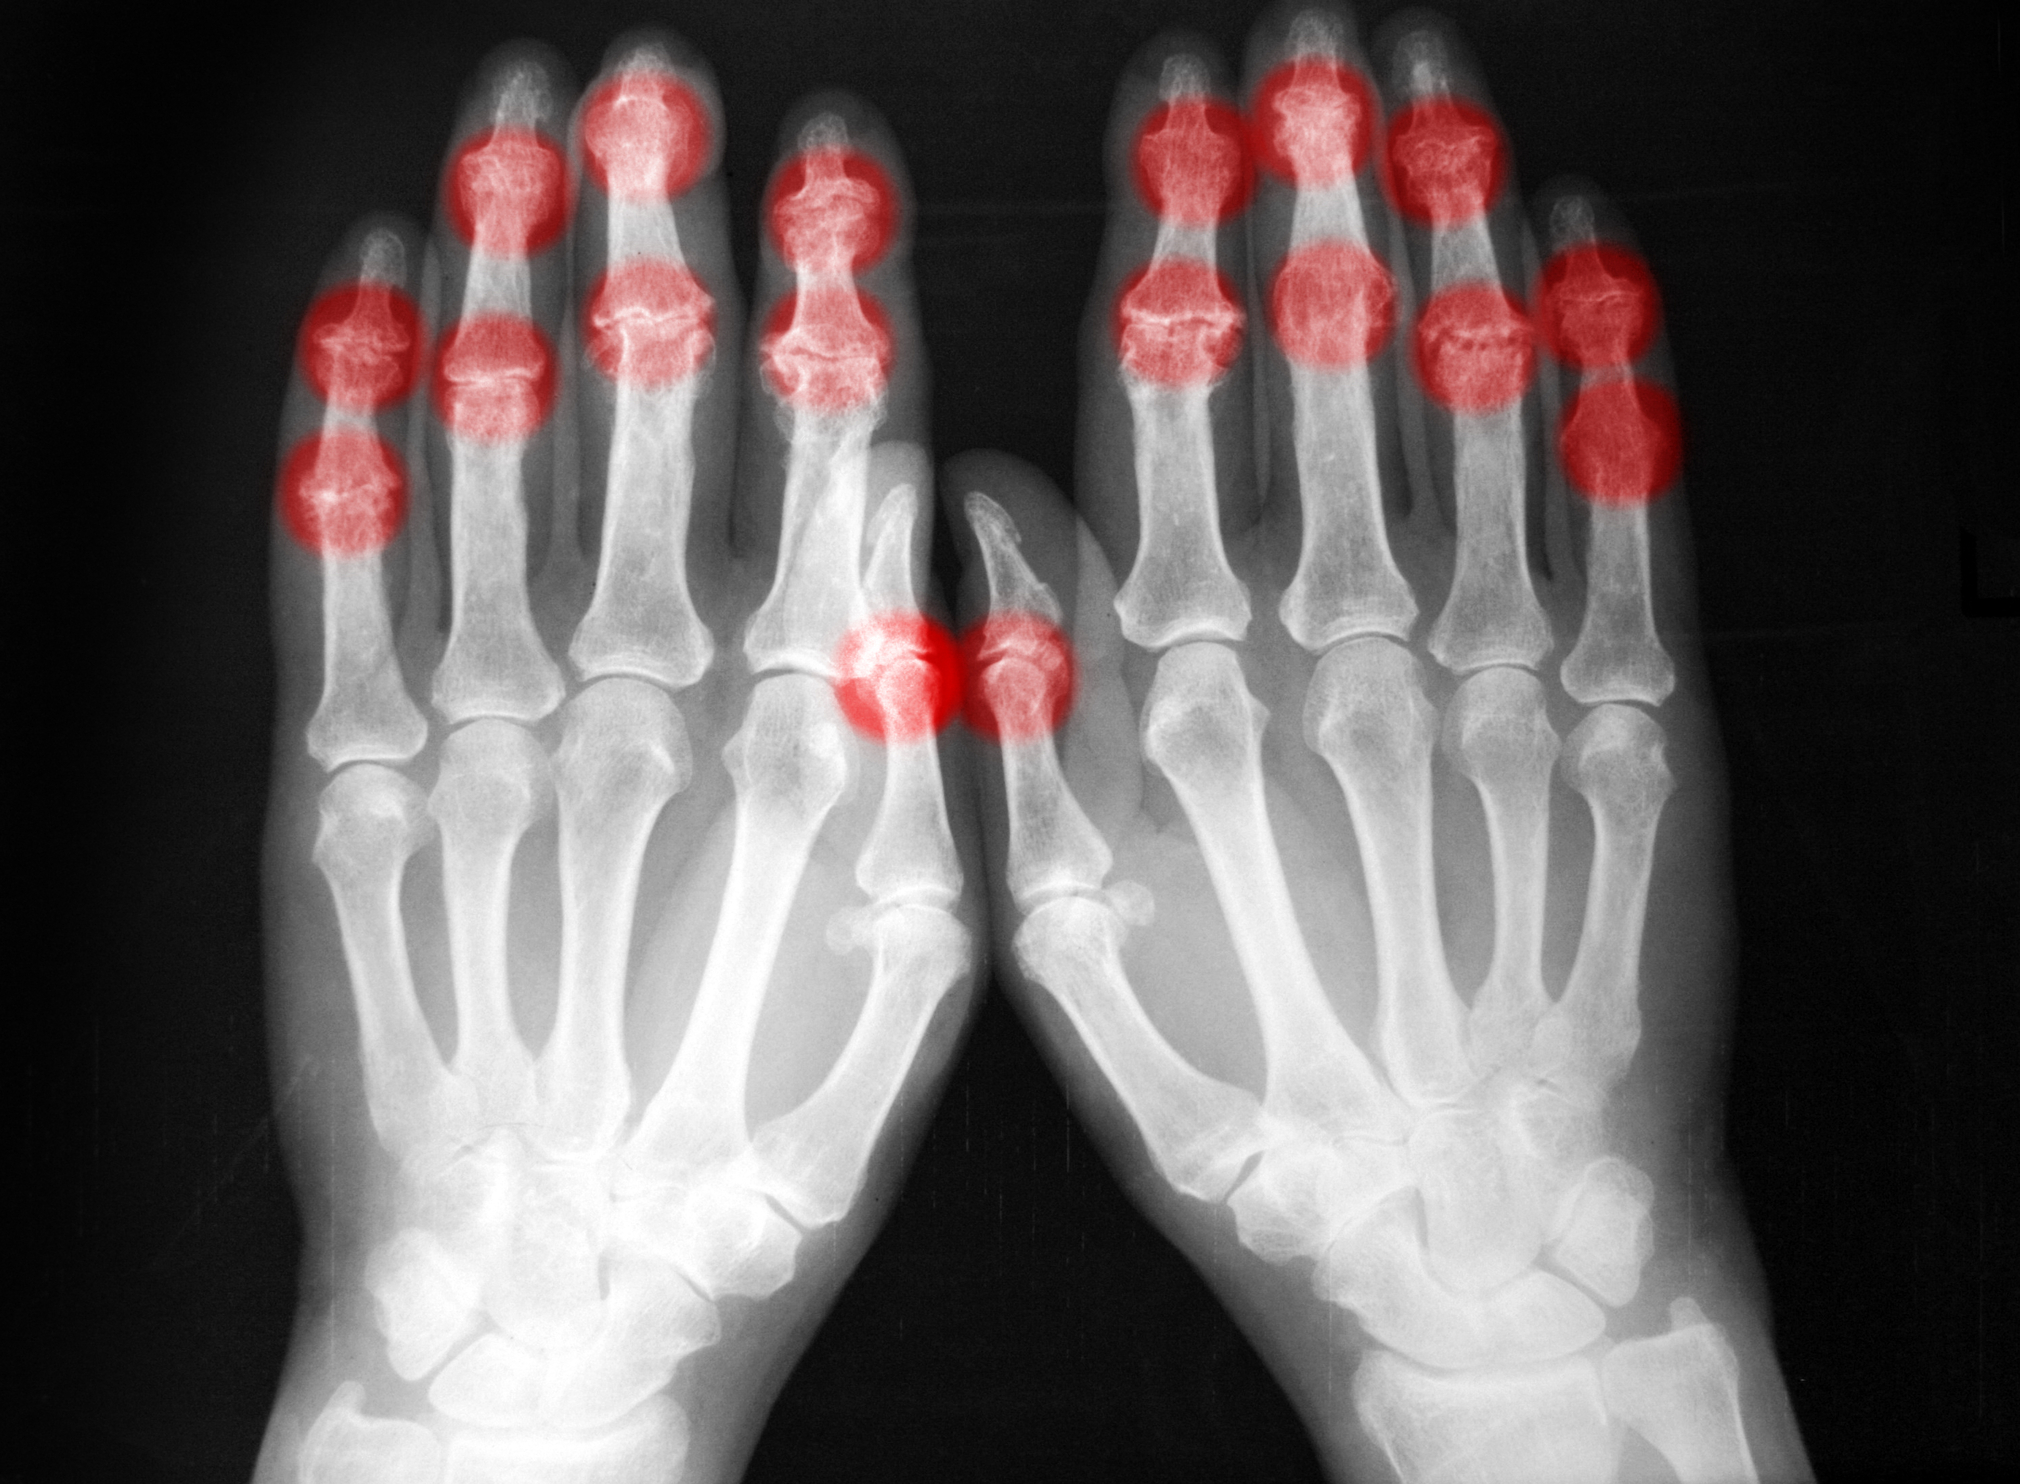

Heberdenov vozlič je kostni izrastek distalnega interfalangealnega sklepa (DIP), Bouchardov vozlič pa kostni izrastek proksimalnega interfalangealnega sklepa (PIP).

Diagnostika Heberdenovih in Bouchardovih vozličev temelji na kliničnem pregledu prstov, ki vključuje oceno simptomov, pregled sklepov in njihove gibljivosti ter palpacijo za odkrivanje morebitnih manjših vozličev.

Rentgenski posnetki nam pomagajo pri potrditvi prisotnosti vozličev in hkrati ocenijo resnost degenerativnih sprememb sklepnega hrustanca. V redkih primerih lahko zdravnik za natančnejšo oceno stanja, ali pri nejasnih znakih, predlaga tudi slikanje z magnetno resonanco (MRI) ali ultrazvok.